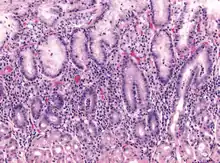

Micrograph showing gastritis. H&E stain.

Gastritis is inflammation of the lining of the stomach.[1] It may occur as a short episode or may be of a long duration.[1] There may be no symptoms but, when symptoms are present, the most common is upper abdominal pain (see dyspepsia).[1] Other possible symptoms include nausea and vomiting, bloating, loss of appetite and heartburn.[1][2] Complications may include stomach bleeding, stomach ulcers, and stomach tumors.[1] When due to autoimmune problems, low red blood cells due to not enough vitamin B12 may occur, a condition known as pernicious anemia.[3]